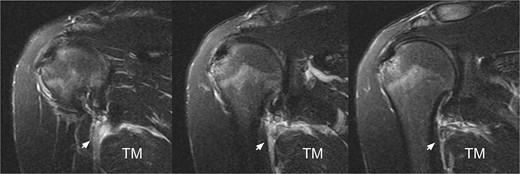

A 23-year-old left-handed male professional gymnast experienced sudden pain and loss of strength in his left shoulder during an extension movement on parallel bars, during training. Two days post-injury, he presented with deformity in the left dorsal region (Fig. 1), pain on palpation in the teres major and latissimus dorsi areas, and a full range of motion but reduced strength in extension and lateral rotation compared with the right shoulder. Neurological examination was normal. He denied any comorbidities or anabolic steroid use. Radiographs were unremarkable, but a T2-weighted magnetic resonance imaging (MRI), performed 1 week after the injury, showed a hyperintense signal at the myotendinous junction of the teres major (Fig. 2).

T2-weighted MRI revealing a hyperintense signal at the myotendinous junction of the teres major, indicated by the white arrow.